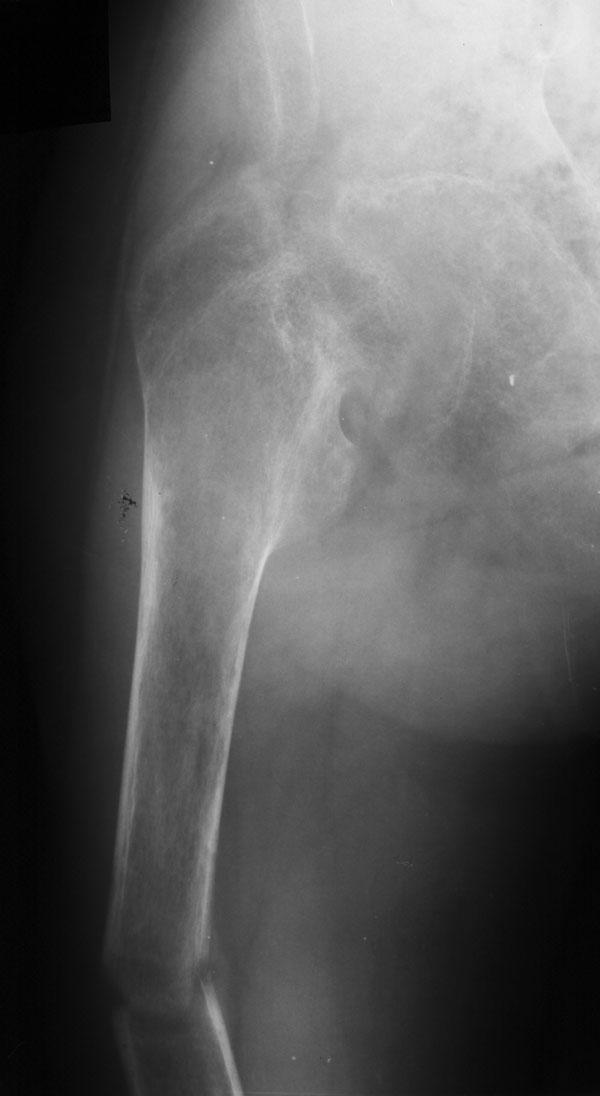

Выписка из амбулаторной карты пациента, 1980 г.р.Находится под наблюдением в поликлинике КНЦ РАН. Состоит на "Д" учёте по заболеваниям:Ювенильный идиопатический генерализованный остеопороз. Деформация грудной клетки за счёт множественных переломов грудины, рёбер. S-образный кифосколиоз грудного отдела позвоночника.Синдром гипофосфатемии неясного генеза. ВСД по кардиальному типу.Инвалид 1-й группы с детства. Последние 4 года не может передвигаться, возникают патологические переломы. Живёт в семье, материально-бытовые условия удовлетворительные.За последние 2 года состояние значительно ухудшилось - усилилась общая слабость, участились патологические переломы, которые не срастаются. Постоянно лежит в постели. Постоянный приём препаратов кальция и диеты с повышенным содержанием кальция, фосфора и белка эффекта не дают. С 11.07.2002 по 30.07.2002 г. лечился в травматологическом отделении АЦГБ с переломом костей правого предплечья со смещением. С 24.08.2002 по 08.09.2002 г. лечился в терапевтическом отделении по поводу острого бронхита с бронхоспастическим компонентом.На сегодняшний день статус. Состояние относительно удовлетворительное. В сознании. Положение вынужденное: сидя в инвалидном кресле, сам встать на ноги и передвигаться не может, туалет только с помощью родственников. Бледный, астеничный. Выраженная деформация грудной клетки, выраженный кифоз и сколиоз грудного отдела позвоночника. Экскурсия грудной клетки ограничена. Участие в акте дыхания вспомогательных межрёберных мышц. Пальпация грудной клетки безболезненна. Деформация всех крупных и мелких суставов за счёт увеличенных эпифизов. Деформация длинных трубчатых костей, мышцы рук и ног атрофичны. Температура - 36,8, ЧД - 29 в минуту. Дыхание жёсткое, проводится во все отделы. Слева от угла лопатки и в аксиллярной области влажные мелкопузырчатые хрипы, в межлопаточной области с обеих сторон свистящие хрипы. Пульс 90 ударов в минуту, ритмичный, симмитричный, слабого наполнения и напряжения. АД 120\80 мм рт. ст. Границы относительной сердечной тупости не расширены. Тоны сердца громкие, ритм правильный. Язык влажный, блестит. Живот при пальпации мягкий, не вздут, симметричный, участвует в акте дыхания, безболезненный. Печень по краю рёберной дуги. Стул регулярный, оформлен, без патологических примесей. Мочеиспускание свободное, безболезненное. Симптом Пастернацкого отрицателен с обеих сторон. Отёков нет.Анализ крови общий 26.08.2002: Hb-146 г\л, Эр.-4,8, ЦП-0,91, Лейк.-6,4, п.-4, с.-45, э.-5, м.-11, СОЭ-4 мм\ч.Анализ мочи общий 26.08.2002: Уд. вес-1025, белок-0,01, сахар-нет, лейк.-0-1 в поле зр., слизь+++, бактерии+.Анализ крови биохимический 26.08.2002: глюкоза-4,9, АЛТ-0,3, АСТ-0,5, биллирубин-11,9, креатинин-44,2, мочевина-3,8, СРБ (+).Анализ крови на микрореакцию - отрицательный.Флюрограмма за 2002: Резко выраженная деформация грудной клетки за счёт множественных переломов рёбер, грудины. Инфильтративных теней в лёгких не определяется. По сравнению с предыдущим исследованием от 01.12.2000 г. - ухудшение: нарастают деформация грудной клетки и позвоночника.ЭКГ за 2002 год: Синусовая тахикардия с ЧСС 88 в минуту. Отклонение ЭОС вправо. Признаки нарушения процессов реполяризации миокарда задней стенки левого желудочка. Повидимому, изменения ЭКГ обусловлены позиционными изменениями, возможно астеничным телосложением.Дополнительные методы исследования.Рентген правого предплечья (17.10.2002): Металлоостеосинтез по поводу перелома обеих костей правого предплечья в н\з: признаки репарации практически не определяются, сохраняется диастаз между отломками.Рентген правого предплечья (24.04.2003): Металлоостеосинтез по поводу перелома обеих костей правого предплечья в н\з: признаки репарации отсутствуют, формируются ложные суставы. Резко выраженный остеопороз.Рентген правого бедра (18.02.2003): Несросшийся перелом правого бедра на границе с\з и н\з со смещением отломков под углом открытым кнутри. Формирующийся ложный сустав. Выраженный остеопороз костей.Рентген правого бедра (24.04.2003): Угловое смещение отломков правого бедра увеличилось. Признаки репарации крайне вялые: по наружному краю отломков формируются замыкательные пластинки - ложный сустав. Выраженный остеопороз.